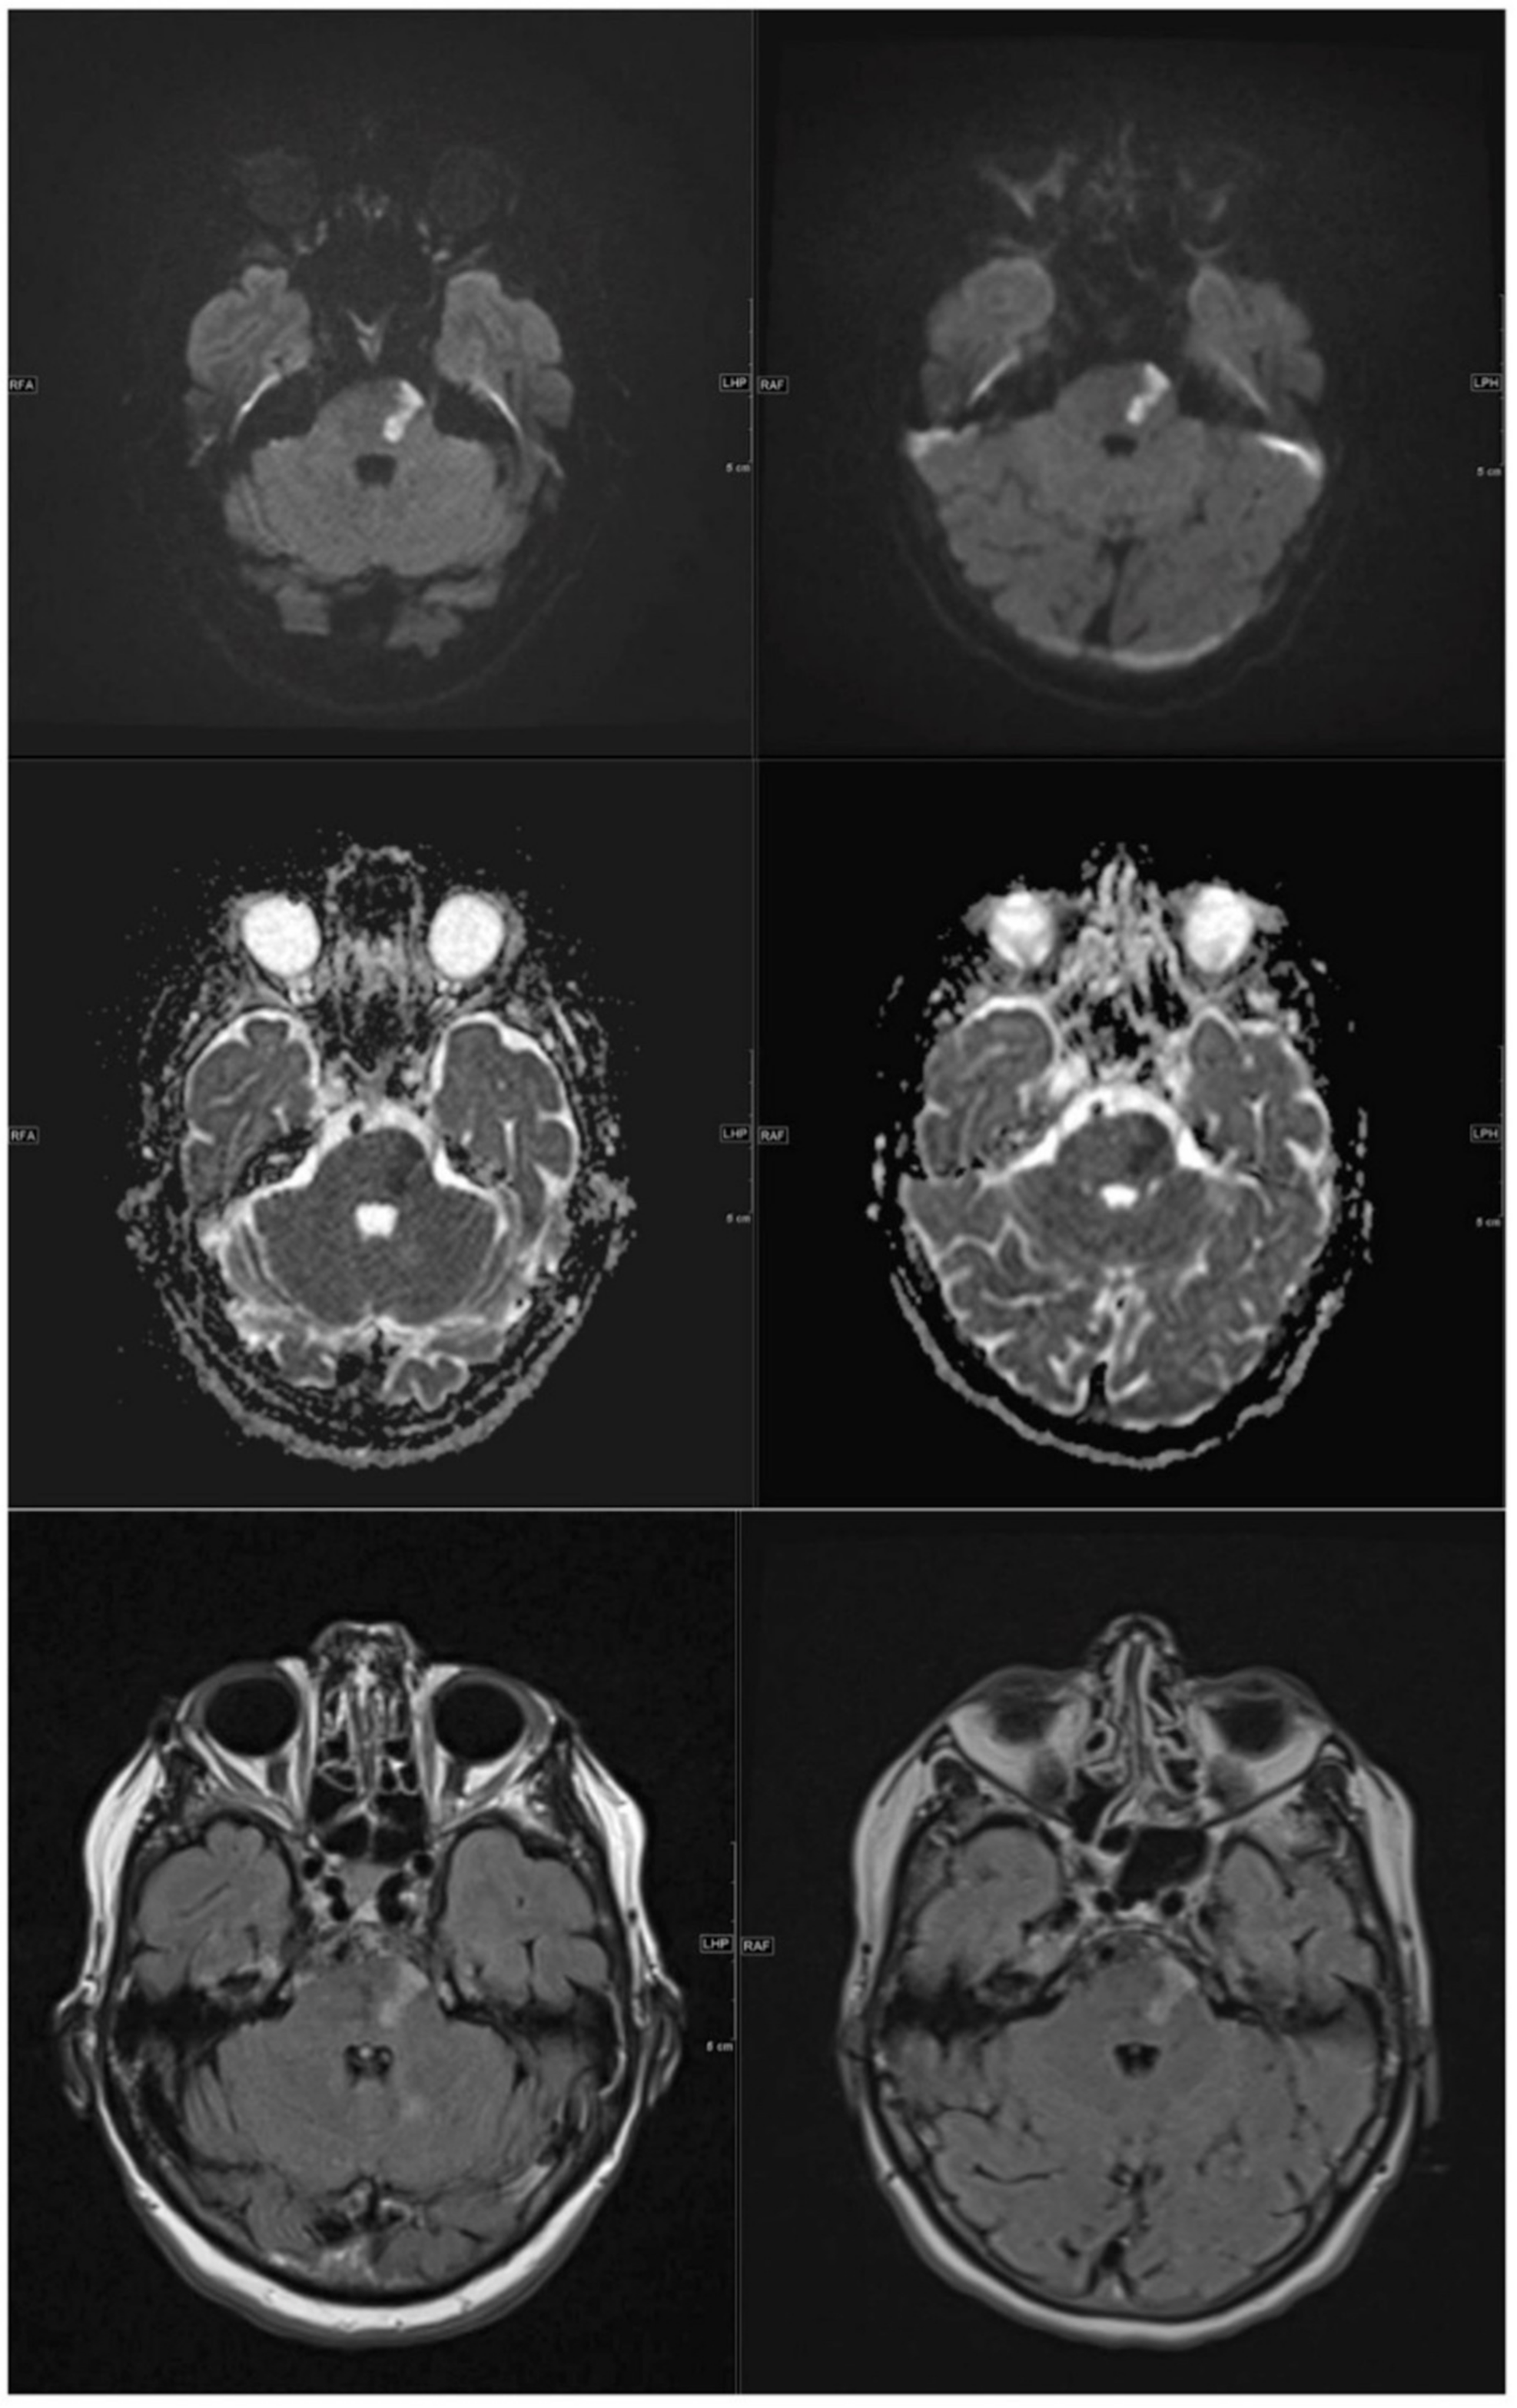

3.1.1. DWI/ADC Datasets

3.1.2. FLAIR Datasets

3.2.1. DWI/ADC Datasets

3.2.2. FLAIR Datasets